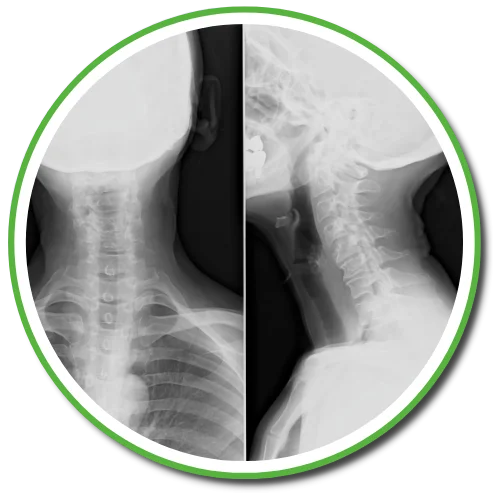

Chiropractors take x-rays to see the internal condition of the spine. X-rays also reveal if there are any underlying spinal disorders, such as arthritis of the spine, abnormal development, disc disorders, bone spurs, and spinal deterioration.

Having an x-ray taken before any adjustment helps chiropractors make a correct diagnosis. Combining x-rays with other exams will benefit the patient ultimately.